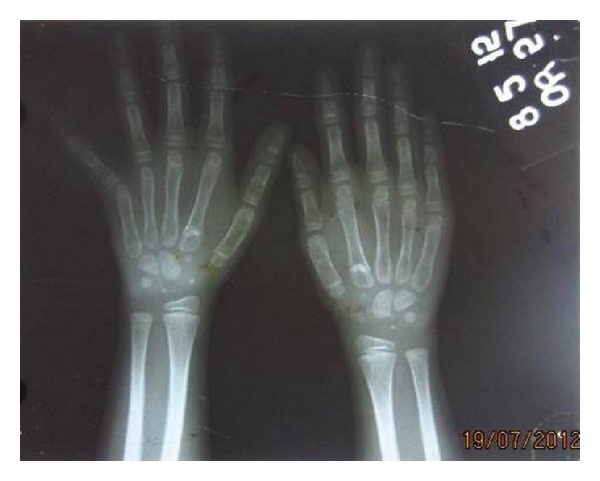

The posteroanterior view of chest radiograph showed normally developed clavicles. Hand wrist radiograph showed short distal phalanges and the bone age was found to be on the lower limit for her age (Figure 6). Thyroid function test was also normal.